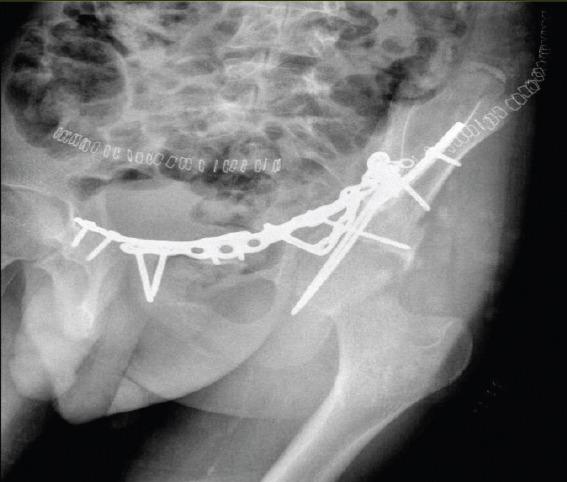

在此,我们报告一例16岁男性,有道路交通事故史,单纯闭合性左髋臼骨折。X线显示双侧髋臼柱骨折伴中心性半脱位。通过改良的Stoppa入路并带有外侧窗口对其进行切开复位内固定治疗。患者在受伤后第6天接受了ORIF。使用钢板和螺钉进行固定。在恢复室,他整个左上肢无法活动且无感觉,而手术肢体的远端神经血管功能正常。恢复15分钟后,感觉恢复,但运动功能障碍持续存在,提示臂丛神经失用。进行了脑部CT扫描,结果未见异常。6个月后,患者自行恢复了感觉,左上肢力量改善至5/5。